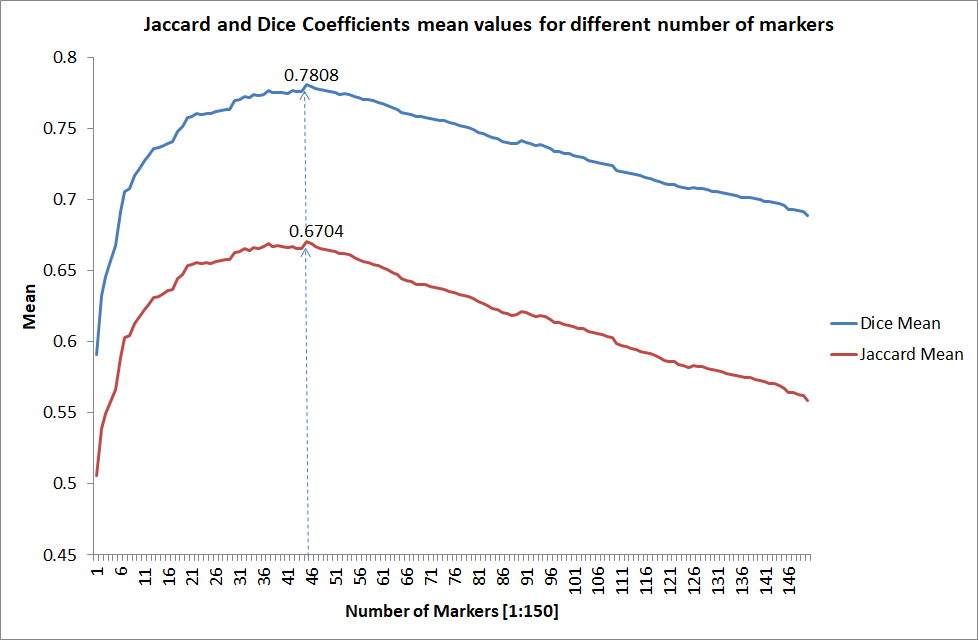

Magnetic resonance imaging (MRI) is an effective imaging modality for identifying and localizing breast lesions in women. Accurate and precise lesion segmentation using a computer-aided-diagnosis (CAD) system, is a crucial step in evaluating tumor volume and in the quantification of tumor characteristics. However, this is a challenging task, since breast lesions have sophisticated shape, topological structure, and high variance in their intensity distribution across patients. In this paper, we propose a novel marker-controlled watershed transformation-based approach, which uses the brightest pixels in a region of interest (determined by experts) as markers to overcome this challenge, and accurately segment lesions in breast MRI. The proposed approach was evaluated on 106 lesions, which includes 64 malignant and 42 benign cases. Segmentation results were quantified by comparison with ground truth labels, using the Dice similarity coefficient (DSC) and Jaccard index (JI) metrics. The proposed method achieved an average dice coefficient of 0.7808 0.1729 and Jaccard index of 0.6704 0.2167. These results illustrate that the proposed method shows promise for future work related to the segmentation and classification of benign and malignant breast lesions.

We tested the algorithm by varying the number of markers between and . Fig 2 describes the segmentation results obtained using different numbers of markers. This plot indicates that markers were found to be optimal using this segmentation approach, yielding satisfactory results.

To evaluate the performance of the proposed method and compare the segmentation results with their corresponding ground truth labels, two well-known similarity metrics are used: (1) the Dice similarity coefficient (DSC), which measures the overlap between two segmentation masks and is sensitive to the lesion size, (2) the Jaccard index (JI), which denotes the average distance between two segmentations [4]. The metrics are defined as:

where refers to the ROIs segmented by our algorithm and is tumor area as determined by manual segmentation. Table 1 summarizes the segmentation accuracy achieved using the proposed method for all 106 cases. The average dice coefficient was found to be 0.780.17 and average Jaccard index was 0.670.21. Fig 3 demonstrate four sample segmentation outputs which are overlaid on manual segmentations provided by two radiologists. It can be seen, that the proposed method could accurately segment the lesions with some marginal errors for medium to large tumors. However, for cases comprising disjoint lesions, the method failed to segment all small lesions and in some cases incorrectly labeled healthy tissue as lesions. This is because in some cases there is a high degree of overlap in the intensity distributions of healthy breast tissue and lesions, and the ROI drawn by the radiologist is very large in the case of disjoint lesions, in order to cover the entire area over which multiple lesions are distributed.

| MCWT | 0.78080.1729 | 0.67040.2167 |

Segmentation of breast lesions in MR images has been tackled previously in various studies, however, very few have employed the marker-controlled watershed transformation approach for this purpose. In this paper, we proposed a novel marker-controlled watershed transformation approach by selecting the brightest pixels as markers in the ROIs. In terms of complexity, this method is simpler and robust in comparison to conventional marker-based watershed methods which used complex features to determine external and internal markers. However, the diversity of lesion shapes and the presence of multiple disjoint lesions distributed across the breast proved challenging, resulting in low DSC and JI scores in some cases. These preliminary results are encouraging for the application of the proposed approach, as a preprocessing step for subsequent classification of MRI lesions. Manually-created ground truth images are intrinsically subjective and creating such reference images for large data sets is a time-consuming process. In subsequent studies, we will look to extend our proposed 2D watershed algorithm to 3D and combine it with a lesion detection and classification technique, to establish a complete computer-aided-diagnosis system, with minimum manual intervention.